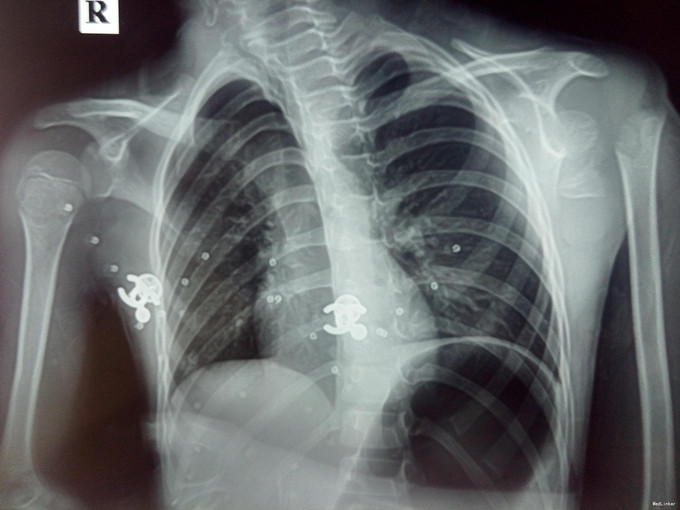

颈肋的x线图片

颈肋的x线图片,颈椎颈肋图片

双侧颈肋并肋骨间骨性联合

20085212011-11-30 15:43:46大家看一下这个颈椎,怎么感觉像 颈肋啊?